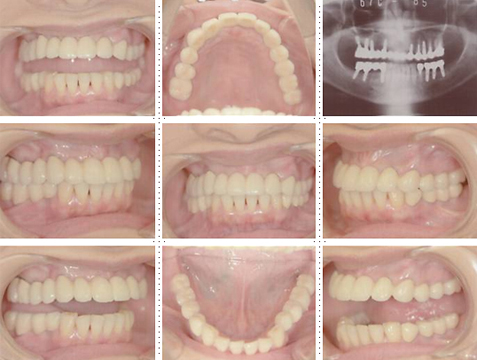

症例1

58才 女性

嘔吐反応が激しく入れ歯を入れると気持ち悪くなってしまうと、インプラント希望で来院されました。

上顎左右奥に4本ずつ計8本のインプラント埋入。下顎左右奥に3本ずつ計6本のインプラント埋入上下顎とも全体的にセラミックを使用した冠をセット。